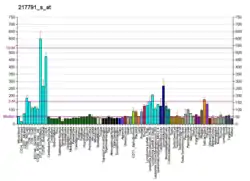

Delta-1-pyrroline-5-carboxylate synthetase (P5CS) is an enzyme that in humans is encoded by the ALDH18A1 gene.[5][6] This gene is a member of the aldehyde dehydrogenase family and encodes a bifunctional ATP- and NADPH-dependent mitochondrial enzyme with both gamma-glutamyl kinase and gamma-glutamyl phosphate reductase activities. The encoded protein catalyzes the reduction of glutamate to delta1-pyrroline-5-carboxylate, a critical step in the de novo biosynthesis of proline, ornithine and arginine. Mutations in this gene lead to hyperammonemia, hypoornithinemia, hypocitrullinemia, hypoargininemia and hypoprolinemia and may be associated with neurodegeneration, cataracts and connective tissue diseases. Alternatively spliced transcript variants, encoding different isoforms, have been described for this gene.[6] As reported by Bruno Reversade and colleagues, ALDH18A1 deficiency or dominant-negative mutations in P5CS in humans causes a progeroid disease known as De Barsy Syndrome.[7]

Function

P5CS catalyzes the phosphorylation- and reduction-conversion of glutamate to Delta-1-pyrroline-5-carboxylate (P5C). This occurs through a process in which glutamate is converted into gamma-glutamyl phosphate in the gamma-glutamyl kinase domain and then the gamma-glutamyl phosphate is the made into gamma-glutamic semi-aldehyde in the gamma-glutamyl phosphate reductase domain. The gamma-glutamic semi-aldehyde is in tautomeric equilibrium with P5C and it is the obligatory intermediate in the interconversions of proline, ornithine, and glutamate.[10] The two isoforms (PC5S.short and PC5S.long) are both involved in different activities as well. The short version has high activity in the gut and is a main participant in the biosynthesis of arginine. The long version of PC5S is expressed in various tissues and is significant for its ability to synthesize proline from glutamate. Also, the short version is inhibited by ornithine, whereas the long version is insensitive to the amino acid.[11]

Clinical significance

Ornithine and/or arginine are key intermediates for the synthesis of urea, creatine, nitric oxide, polyamines, and protein; while proline is a major component of the connective tissue proteins, collagen and elastin. Because all three of these amino acids are a part of very significant processes, the presence of P5CS becomes an important regulator which makes sure that none of these three become deficient.[16] Therefore, a lack of P5CS, due to mutations in the ALDH18A1 gene, often leads to neurodegeneration, joint laxity, skin hyperelasticity, bilateral sub capsular cataracts, and a plethora of other complications associated with impaired proline and ornithine synthesis.[11]